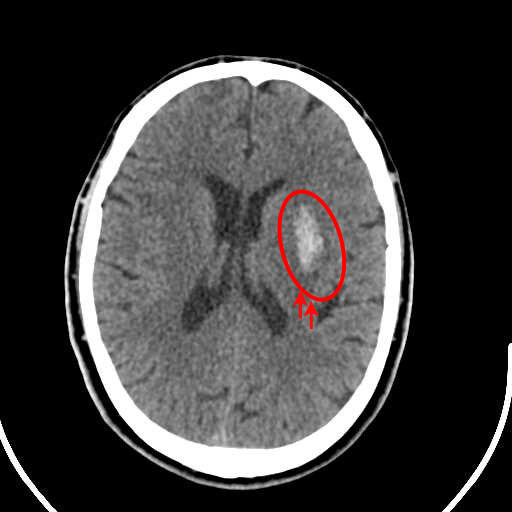

Figure 1: Illustrative examples of different types of brain hemorrhages in CT scans. The hemorrhagic regions are highlighted in red. (a) IPH, (b) IVH, (c) EDH, (d) SAH, (e) SDH.

The dataset used in this study was collected from two medical centers in Tehran, Iran: Rasoul Akram Hospital and Firouzabadi Hospital, over a period spanning 2018 to 2024. All CT scans were manually labeled hierarchically by two board-certified neurosurgeons to ensure accurate classification of ICH subtypes. The labeling process involved an initial annotation by one neurosurgeon, followed by validation and verification by a second expert to minimize errors and inconsistencies. Fig. 1 illustrates representative examples of different ICH subtypes in brain CT scans. The hemorrhagic regions are highlighted in red for better visualization. These annotated examples provide insight into the distinct imaging characteristics of each hemorrhage type, emphasizing the variability in their locations and appearances within the brain. The study received ethical approval, and data collection was conducted in compliance with institutional review board (IRB) regulations and the Declaration of Helsinki, ensuring patient confidentiality and adherence to ethical standards.